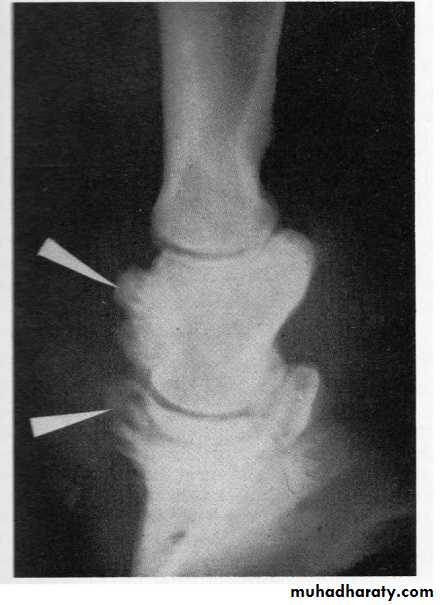

Buttress foot changes on radiograph. The new bone growth is shown by the upper arrow on the middle phalanx. The lower arrow shows new bone growth on the extensor process of the distal phalanx..